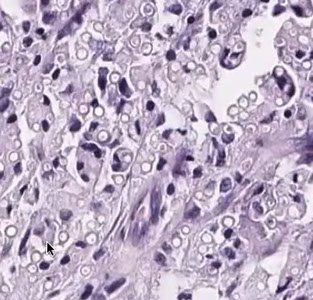

Micro: diffuse infiltrate of large histiocytes c ground glass cytoplasm, like ground glass

IHC: (+) CD45, CD68, CD11b, HAM56

- neg: S100, CD1a

DDx: JXG